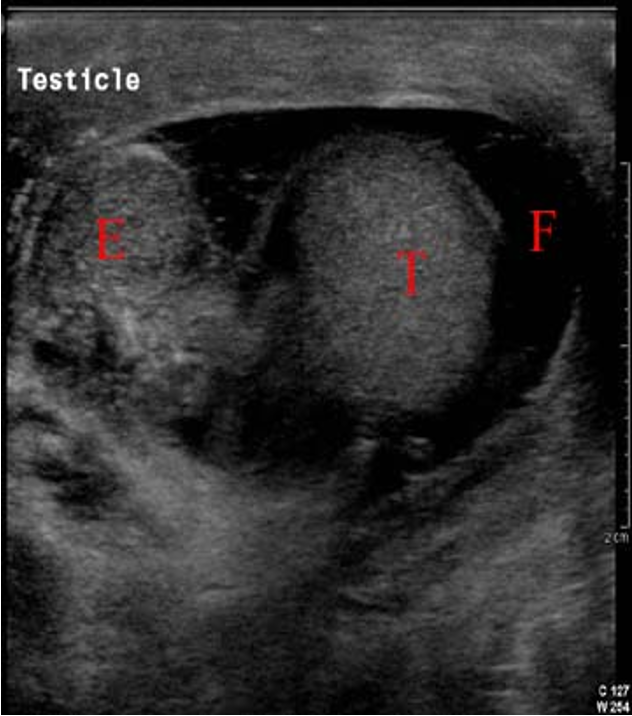

Reactive Hydrocele due to epididymitis